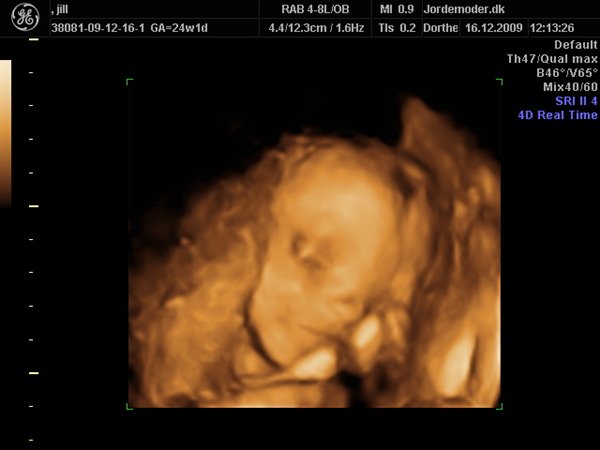

her er lidt fra vores scanning i uge 24+1, hun blev vurderet til 675 g....jeg synes det er vildt så mange detaljer og ansigsudtryk hun havde;-)

derfor glæder jeg mig til at se hende "rigtigt"....synes hun ligner mig som baby...hehe

knus jill